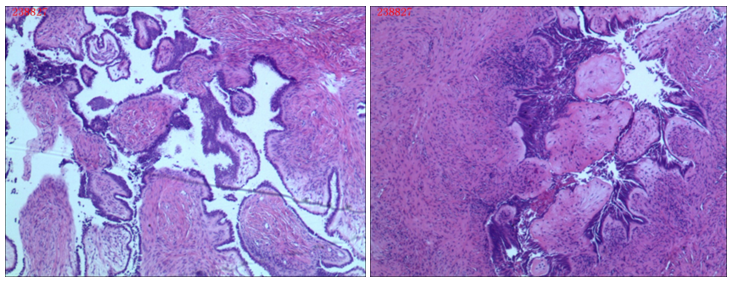

Computed tomography (CT) of the pelvis (Figure 1) showed a cystic mass in the right adnexa suspicious for ovarian borderline epithelial tumor or cystadenocarcinoma. A small amount of free fluid in the cul-de-sac and endometrial thickening were also noted (Figure 1).

Figure 1 CT Scan of pelvis: The volume of the uterus is full, density of uterine wall is well-distributed , endometrium slightly thickened, enhanced scan show no lesions, solid-cystic hypodense shadow was seen in the right-sided adnexa, cystic lesion which is in the size of 4.3cm X 3.8cm X 5.3cm is predominant. In the cystic lesion, we can see line like separate shadow, papillary nodules can be seen in its top wall; papillary nodules are in the size of 1.0cm X 0.6cm X 0.6cm. The demarcation between the lesion and the bladder or adjacent intestine was clear. No lymphadenopathy noted.20